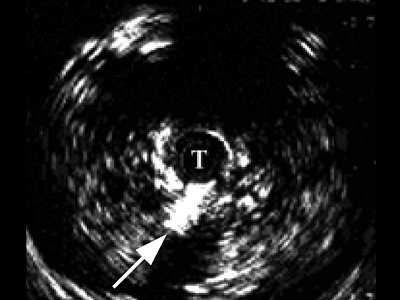

Четко визуализируются патологические образования в паренхиме (рис. 4). В зоне стриктуры мочеиспускательного канала определяется различной протяженности и глубины фиброзная ткань в виде гиперэхогенных участков.

Рис. 4. Эхограмма простатического отдела уретры.

На рис. 5 а представлена нормальная эхограмма губчатой части уретры, на рис. 5 б - эхограмма спонгиозной части уретры в зоне ее стриктуры. Определяется фиброзный участок в виде гиперэхогенного кольца вокруг уретры, затрагивающий всю толщу спонгиозного тела (спонгиофиброз).

б) Зона стриктуры (стрелка).